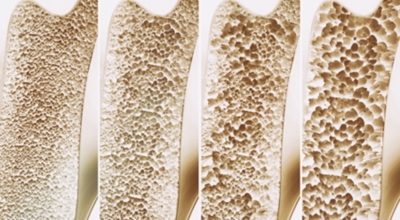

중년에 접어들면 뼈에 좋은 칼슘제과 관절영양제를 찾게 됩니다. 영양제도 좋지만 뼈와 관절에 좋은 운동과 식이요법도 중요해요. 뼈에 이상이 생기면 골다공증으로 이어지므로 특히나 관리를 잘 해야 해요. 일반적인 때에 음식을 통해 어떻게 관리를 하면 되는지 골다공증에 좋은 음식을 알려드리려고 해요.

우유는 탄수화물, 단백질, 지방 등 열량을 내는 영양소뿐 아니라 칼슘, 인, 비타민B2, 비타민A, 마그네슘, 셀레늄 등 여러가지 무기질과 비타민이 다양하게 함유되어 있어요.이러한 만성질환의 위험도를 감소시킬 수 있는 이유는 공액리놀레산이라고 부르는 물질이 있기 때문이예요. 면역체계, 뼈의 밀도, 혈당 조절, 체지방 조절, 심장마비 위험 감소의 위험을 감소하게 만들어 주는 등 다양한 건강에 아주 좋은 영향을 주며 있답니다.

특별히 고령일수록 뼈 건강을 보호해주는 불포화 지방산을 섭취하는것을 통해 골다공증을 방지할수 있어 좋습니다. 국내 연구를 따르면 불포화지방산 섭취에 따른 50대 이상의 여성 골다공증 발병비율을 확인하니 불포화지방산을 복용한 실험군의 발병비율이 약 20% 저감되었다고 발표했습니다. 여러분의 식단에 등푸른 생선등등의 불포화 지방산이 많은 음식을 추가해서 뼈건강을 지켜실수 있도록 해보세요.